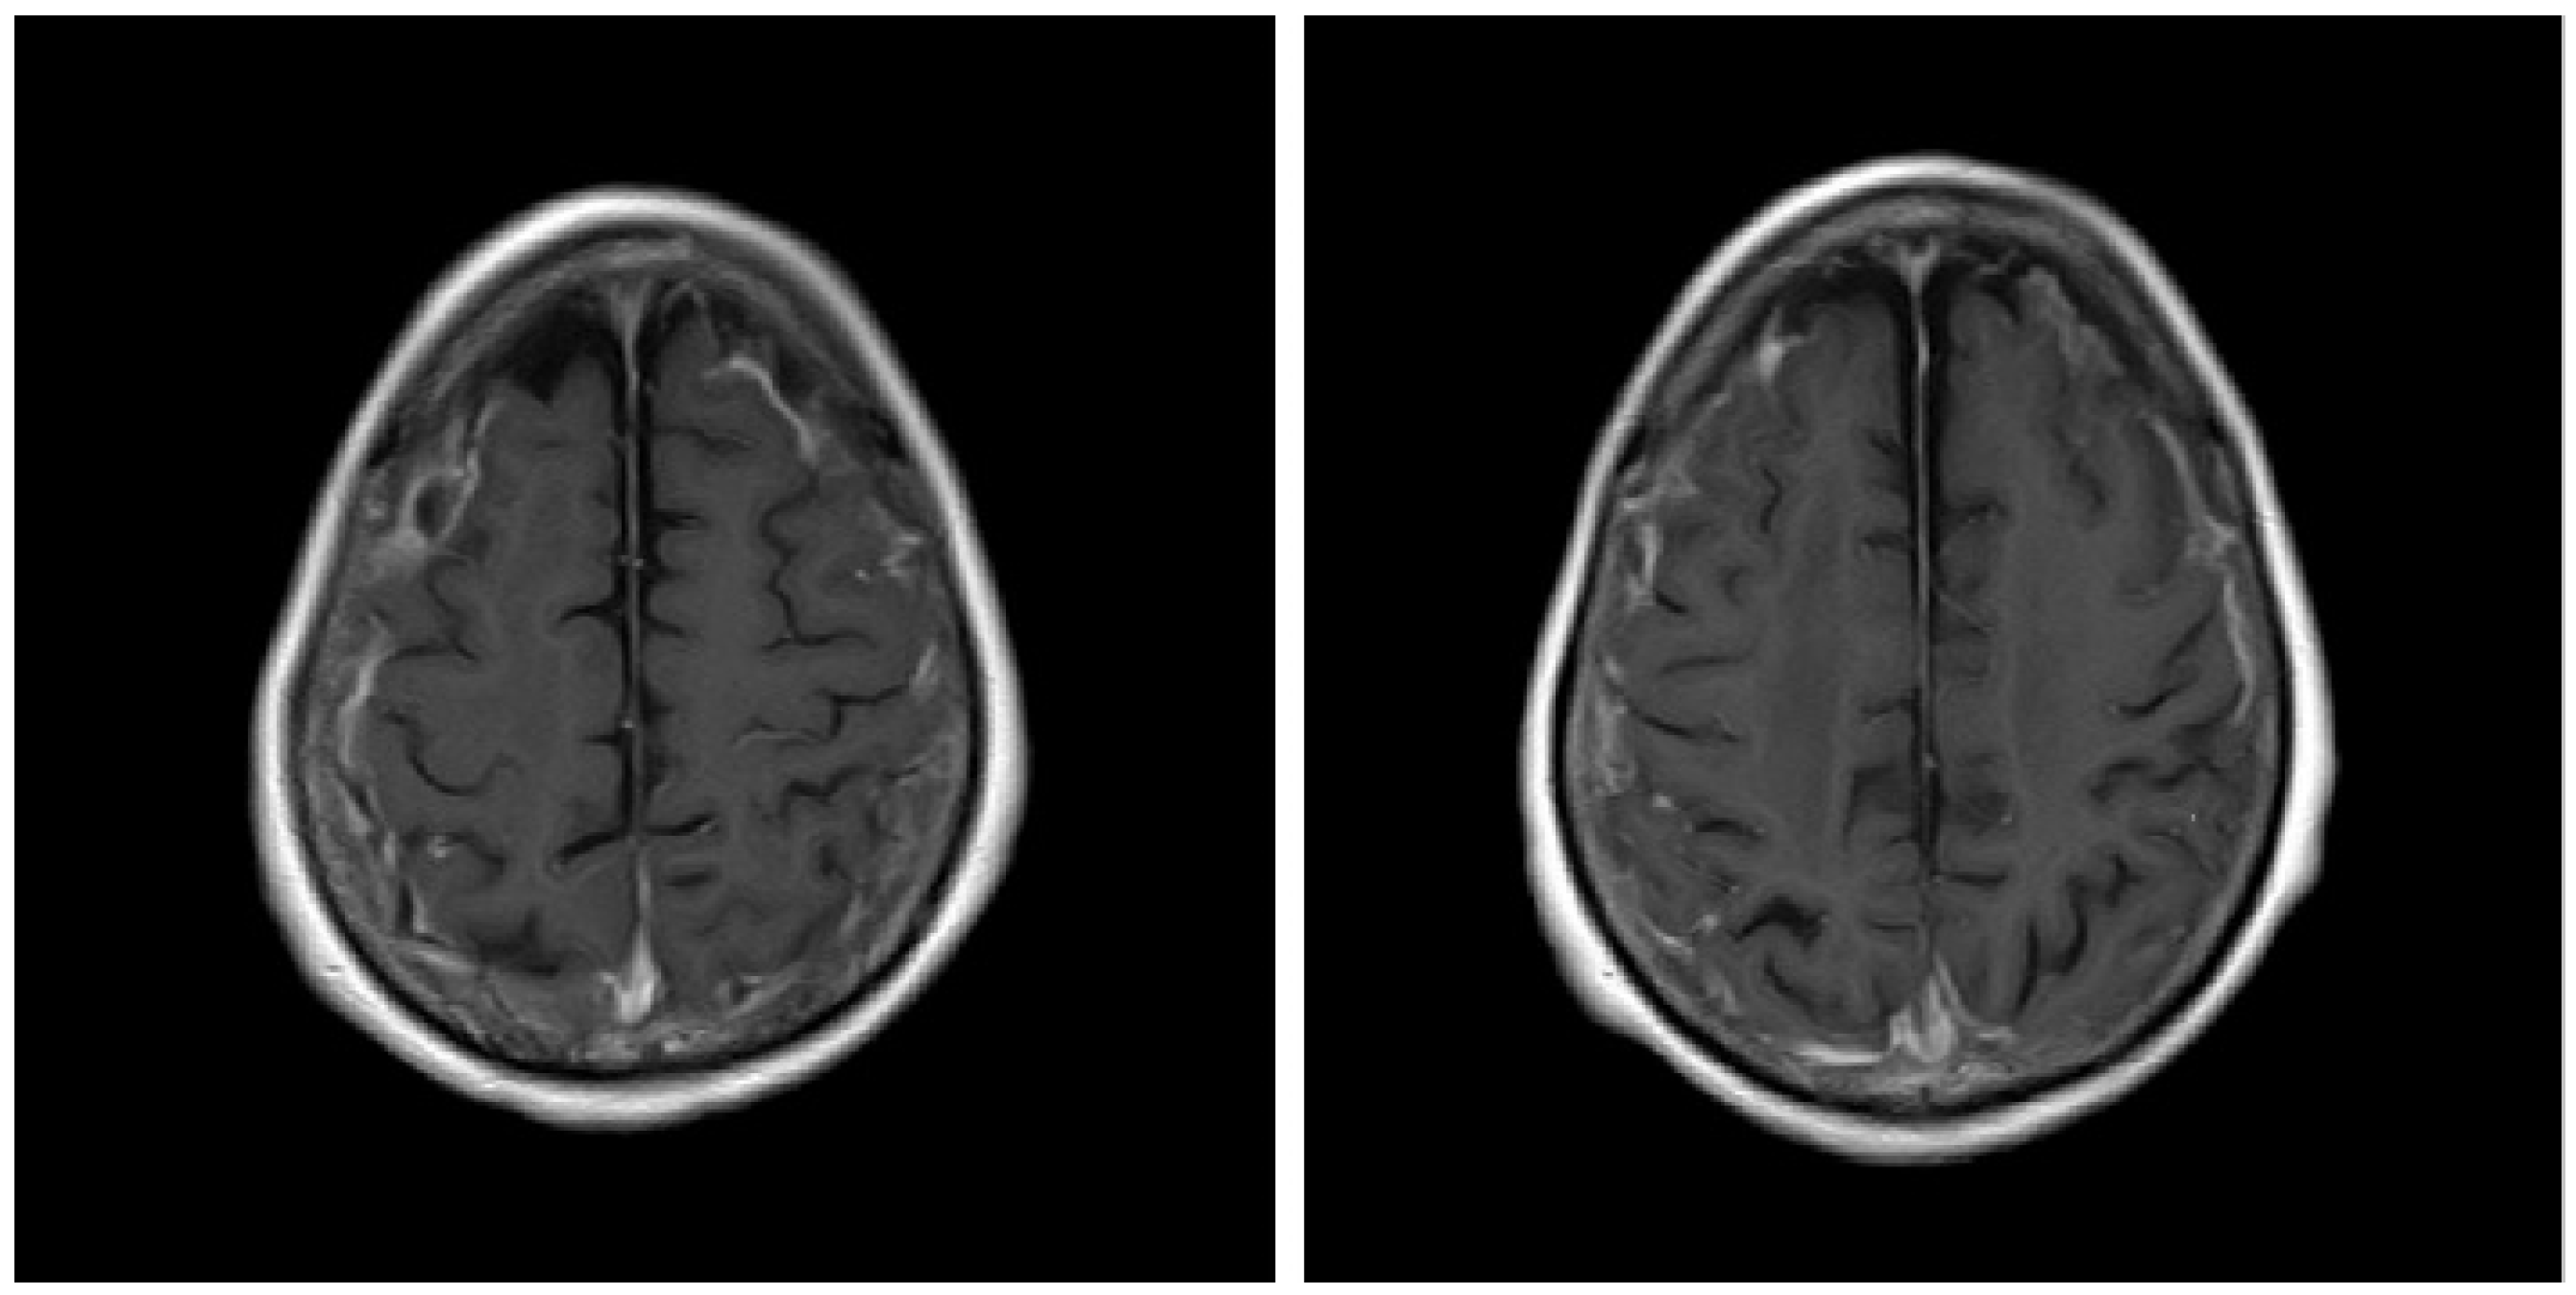

A 74-year-old Japanese woman who was diagnosed with rheumatoid arthritis 12 years earlier was admitted to our hospital. Fourteen months before admission to our hospital, she had discontinued methotrexate treatment due to thrombocytopenia. Nine months before admission, she was admitted to another hospital for status epilepticus, and cerebrospinal fluid (CSF) examination showed normal numbers of cells and protein levels and was negative for fungi, bacteria, tuberculosis, and herpes simplex virus. Three weeks before admission, a brain MRI was performed; fluid-attenuated inversion recovery (FLAIR) MR images showed hyperintensity along the sulci of both fornices, and T1-weighted (T1W1) images showed high signal after gadolinium (Gd) contrast agent administration (Figure 1). Therefore, she was diagnosed with meningitis and admitted to our hospital. On admission, she was taking prednisolone (8 mg/day) for arthritis.

Figure 1.

Gadolinium-enhanced T1-weighted (T1W1) brain magnetic resonance imaging scan before treatment.

In contrast, rheumatoid meningitis presents with characteristic findings on MRI. Brain MRI findings of rheumatoid meningitis are mostly unilateral supratentorial lesions characterised by a high signal on FLAIR and diffusion-weighted imaging (DWI) sequences in the subarachnoid space and a Gd-enhancing effect of the meninges, composed mainly of the pia mater [10]. DWI hyperintensity often persists after the symptoms improve and the Gd-enhancing effect disappears and therefore does not necessarily indicate high activity [10]. In our case, FLAIR and DWI hyperintensity, which had a meningeal Gd-enhancing characteristic of rheumatoid meningitis, was also observed (Figure 1). Therefore, the patient was correctly diagnosed and started early on treatment. Central nervous system disorders associated with rheumatoid arthritis may involve both the pia mater and the dura mater. In cases with dura mater involvement, clinical symptoms such as headaches and cranial neuropathy are common [1]. In cases where the pia mater is affected, convulsion, paralysis, psychiatric symptoms, and gait disorders are common [1]. There are no guidelines for the treatment of rheumatoid meningitis, but previous reports have indicated that the administration of glucocorticoids alone led to improvement [11]. Similarly, our patient was treated with glucocorticoids alone and improved. Recurrent rheumatoid meningitis has also been reported to develop during the administration of infliximab, and anti-TNF-α inhibitors may be ineffective in these instances [12]. Therefore, it is still unclear what strategy is required for recurrence suppression and maintenance. However, rituximab has been shown to be effective in the suppression of rheumatoid arthritis and may potentially be effective in rheumatoid meningitis [12]. Other reports have indicated that the use of immunosuppressants such as azathioprine and cyclophosphamide in combination with glucocorticoids can also successfully treat rheumatoid meningitis [13].